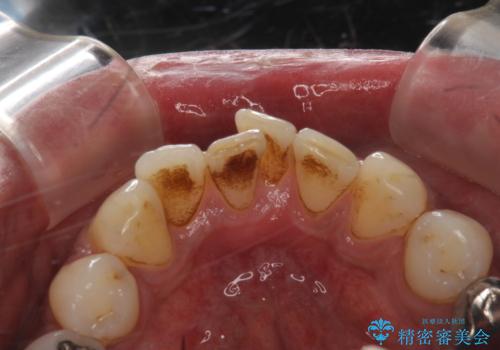

タバコによるヤニをPMTC(歯科医院での専門的クリーニング)で除去。

- タバコのヤニによる着色を気にされ、来院されました。PMTC(歯科医院での専門的クリーニング)をおすすめしました。

歯ブラシでは、除去できない着色、汚れが落ち歯の表面もツルツルになって気持ちがいいと喜んでいただけました。